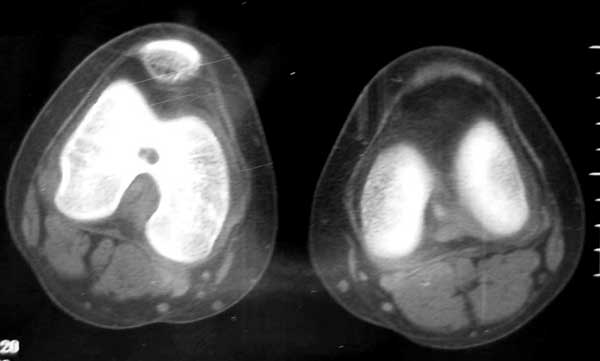

14岁女孩,7月前右膝关节疼痛,进行性加重,无外伤,无潮热盗汗,无高热,未治疗。1周前入院,下肢皮肤牵引,抗炎治疗,症状减轻。入院查右膝关节轻肿,浮膑(-),碱性磷酸酶140,余(—)。如何诊治?1周前ct 见关节面破裂,关节腔穿刺少量血性液:细胞学检查示滑膜炎改变,培养未见细菌生长。 7月前ct

6月前mri,1周前ct

病变骨质增生硬化,不支持结核。mri示病变中心内短t1、长t2信号,考虑为骨样骨瘤并瘤巢内出血。

病变特点:股骨的非负重区的破坏病灶,病灶边沿的硬化明显,ct mri均显示病变为慢性过程,关节积液不明显,考虑低毒感染可能性大,请继续抗炎治疗,不除外骨样骨瘤

病变特点:病灶较小,周围硬化环厚/明显,中心ct呈透光区,mr可见液性成分;14岁小孩,骺端关节面的病变,可考虑的病变有:1/低毒力感染,嗜酸性肉呀肿,2/软骨母细胞瘤,年龄/好发部位/信号/密度均可符合诊断,唯一不支持的是病灶中心未见点状钙化或骨化影3/腱鞘囊肿4/巨细胞瘤和骨囊肿可以不考虑。

骨骺轻度水肿,近髁间凹关节面侧骨局灶性破坏,病灶边缘有较多的环形硬化,骨显著硬化是细菌性感染的特点,关节积液不明显...抗炎治疗症状减轻,考虑为低毒感染可能性大(brodie骨脓肿可能).请继续抗炎治疗